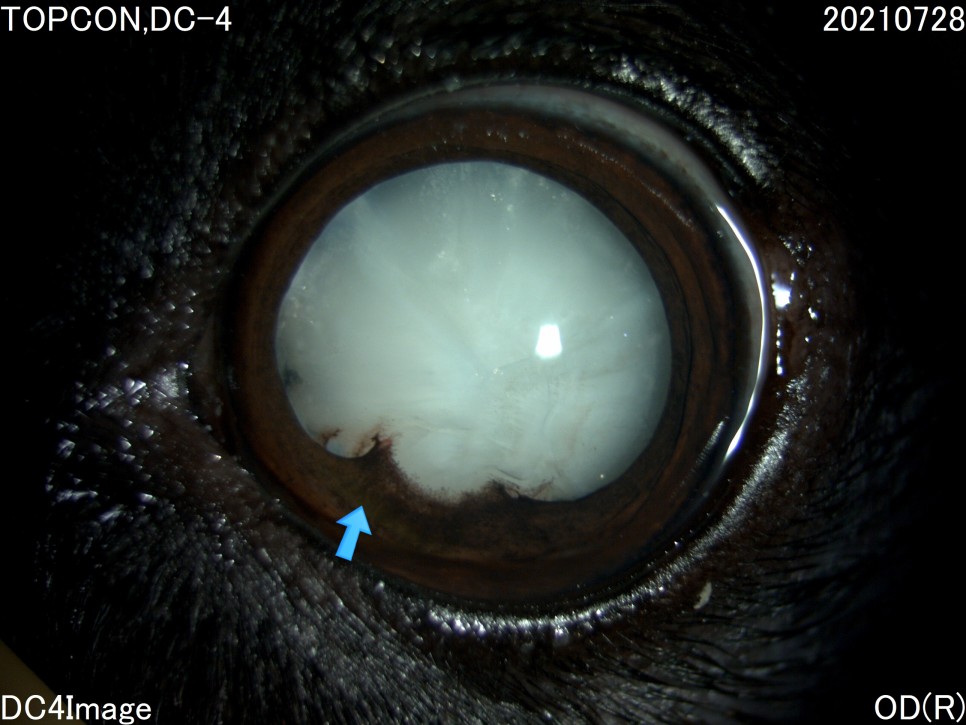

- 세극등 현미경 검사

양안의 백내장이 심하게 진행되고 있었지만 다행히도 당뇨병 관리를 하고 있는 전주 24시 동물병원은 당뇨병 관리 뿐만 아니라 눈 관리도 계속해 주셨기 때문에 내원 당시에는 양안 모두 심한 포도막염은 없었습니다.

그러나 왼쪽 눈은 백내장 단계 중 4기인 과성숙 단계로 진행되었으며, 이전에 앓고 있던 심한 포도막염에 의해 홍채의 일부가 수정체에 유착되어 있는 것이 보였습니다.

백내장이 오래 되거나 염증 반응이 심한 경우는 수정체를 감싸는 낭포 섬유화가 일어나 낭 자체에 백내장 파편이 붙어 있을 수 있는데, 자녀분이 바로 그런 상태였습니다.이런 경우 수술이 어려울 뿐만 아니라 수술 후 합병증의 발생률도 더욱 높아질 수 있습니다.